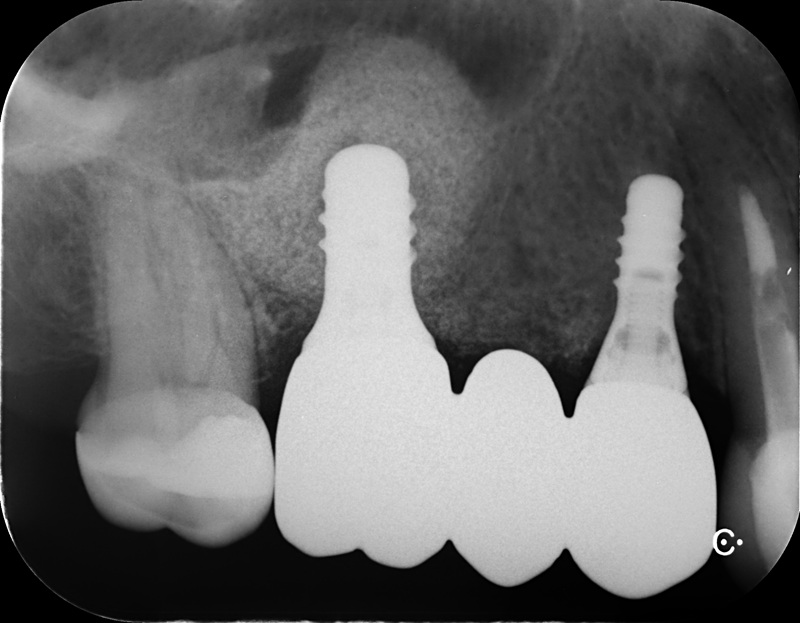

| 治療名 | 抜歯即時インプラントとソケットリフトによる上顎臼歯部の修復症例 |

| 治療説明 |

歯の根が破折していたため抜歯が必要となり、患者さんとご相談のうえ、インプラントによる治療を選択しました。 ただし、インプラントを支える骨の高さが不足していたため、**上顎洞に骨を足す“ソケットリフト”**を併用し、安全にインプラントを埋入しました。 |

| 治療回数・期間 | 約3ヶ月 |

| 副作用とリスク |

・入れ歯や従来のブリッジと比べて、治療期間が長くなる傾向があります。 |

| 料金(税込) | 小規模GBR:110,000円 ソケットリフト:165,000円 インプラント一次手術:220,000円 二次手術:55,000円 上部構造〈セラミック〉:165,000円 合計:715,000円 |